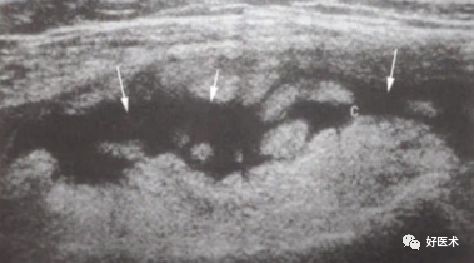

超 声

(1)关节积液:尤其是髌上囊及左右侧囊

(2)关节内病变:滑膜弥慢性增生、肥厚,可见大小不等形状不规则的实性团块状回声,呈低、中等或高回声,分布不均匀;半月板及交叉韧带边缘模糊不清,股骨或胫骨边界不光滑或局部呈锯齿状改变

(3)关节外病变:周围软组织内有结节状或分叶状不均质回声区

髌上囊多个等回声结节,可见绒毛状突起

髌上囊内液性暗区,滑膜不同程度增厚,呈结节状